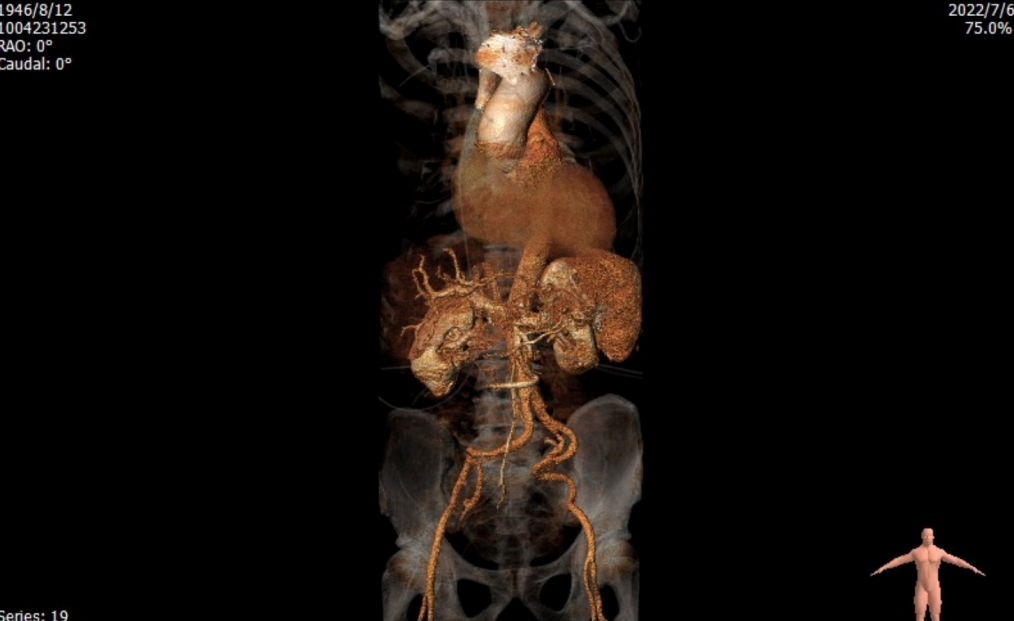

入路情况

血管入路严重迂曲

• 入路右侧分叉高度可、轻度迂曲,右侧血管平均最小内径5.0mm。左侧分叉高,重度迂曲,左侧血管平均最小内径6.0mm。

• 主动脉弓部角度虽不大,但伴有轻度升主动脉扩张的现象,不排除术中使用抓捕器跨瓣的可能。

• 右侧血管虽较为纤细,然左侧分叉高,且血管入路重度迂曲,拟以右侧股动脉为主入路;